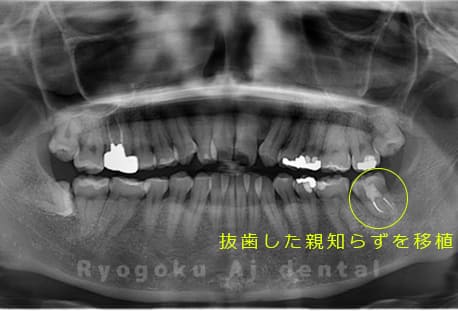

Case27

-

重度カリエス

歯牙移植咬合面術前 -

移植する親知らず

歯牙移植術直後咬合面

歯牙移植術後咬合面

歯牙移植術前側面

歯牙移植術中側面

歯牙移植術後側面

- 原因

- 重度カリエス

- 治療内容

- 自家歯牙移植、部分矯正

- 治療費用

- 220,000円(移植費用)

110,000円(部分矯正費用)

虫歯が大きく、保存不可能となった歯を上の親知らずと交換する自家歯牙移植を行いました。移植歯が小ぶりであったため、部分矯正を行い問題なく噛み合い、経過良好です。